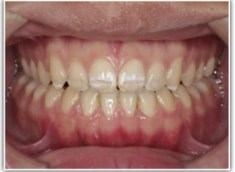

開咬(かいこう:オープンバイト)ケース

治療法:表の矯正(T21ブラケット)

(インプラントアンカーや外科矯正は行わず、エラスティックと機能訓練のみ)

治療後(2年2ヶ月後)